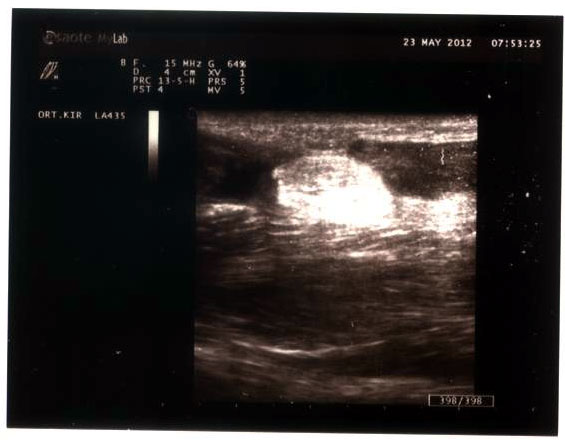

Ultralyd af achillessene efter 4 uger

Video af achillessene ruptur 4 uger efter skaden dynamisk undersøgelse